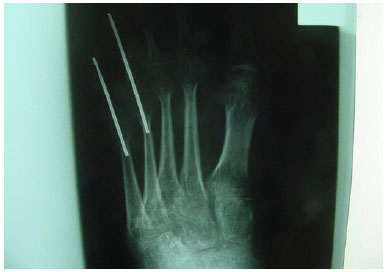

The patient was a 20-year-old woman who had a motorcycle accident, wherein she sustained foot trauma with loss of back substance at the level of the first to fifth metatarsus, with bone and tendon exposure (Figure 1) and fracture of the fourth and fifth orthopedically treated metatarsus (Figure 2).

Figure 2. Fracture of the fourth and fifth metatarsals treated with fixation.